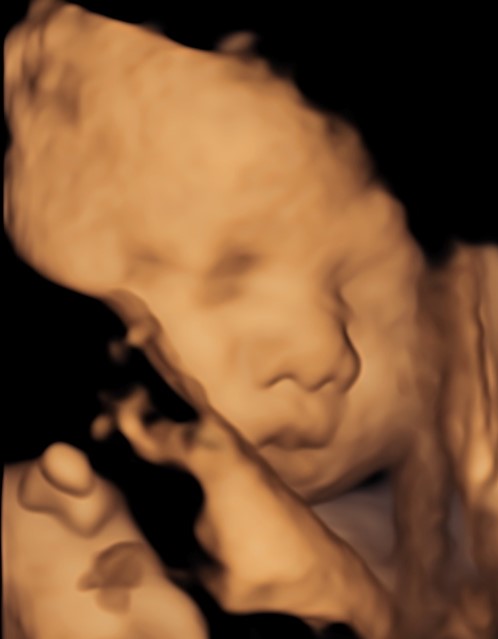

4D/5D/HD Ultrasound Gallery

Gallery